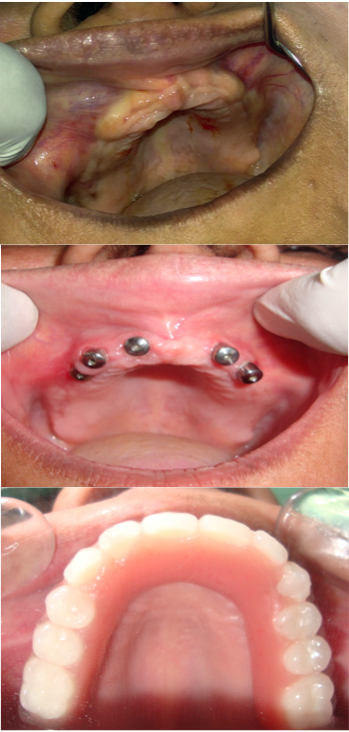

Full Mouth Rehabilitation